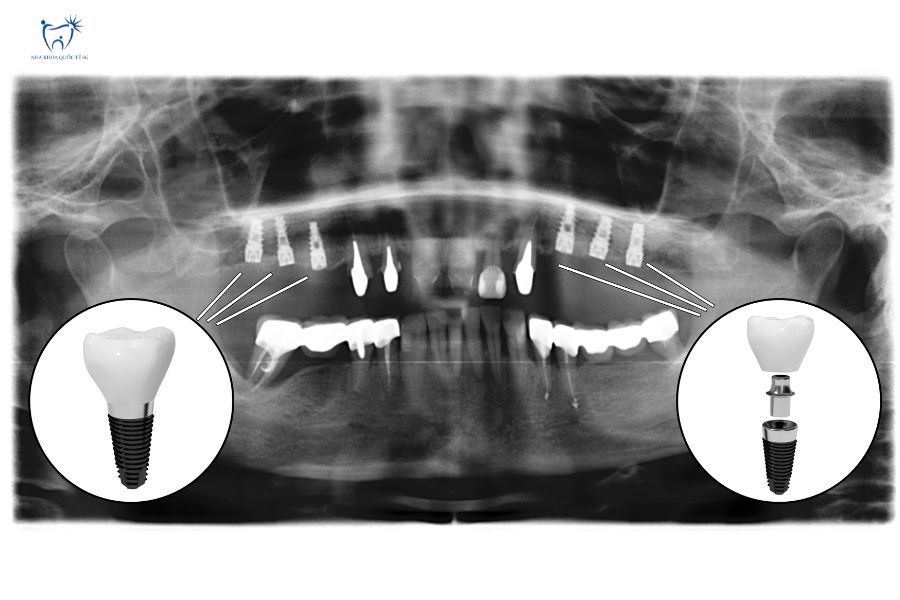

Hình X-Quang chụp CT – Conebeam sau khi cấy ghép implant

Ưu điểm vượt trội của Implant:

- Không cần mài răng thật bên cạnh

- Ngăn chặn tiêu xương hàm

- Tuổi thọ 20+ năm, có thể trọn đời

- Khả năng nhai tương đương răng thật 90%

Theo International Team for Implantology, tỷ lệ thành công của implant sau 10 năm đạt 95-98% khi được thực hiện đúng kỹ thuật.

Chi phí: 20.000.000 – 40.000.000đ/trụ (bao gồm trụ Implant + abutment + mão sứ)